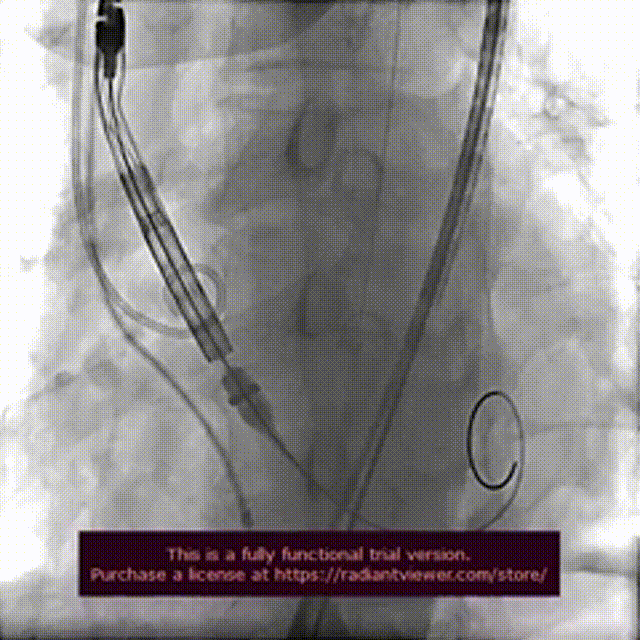

术前造影检查,主动脉瓣大量返流

圈套器辅助下,送入30mmVitaflow瓣膜

造影定位,可见无冠瓣叶较高

快速起搏条件下前期释放2/3瓣膜

造影显示瓣膜位置良好后完全释放

术后造影

数字减影模式检查下肢血管